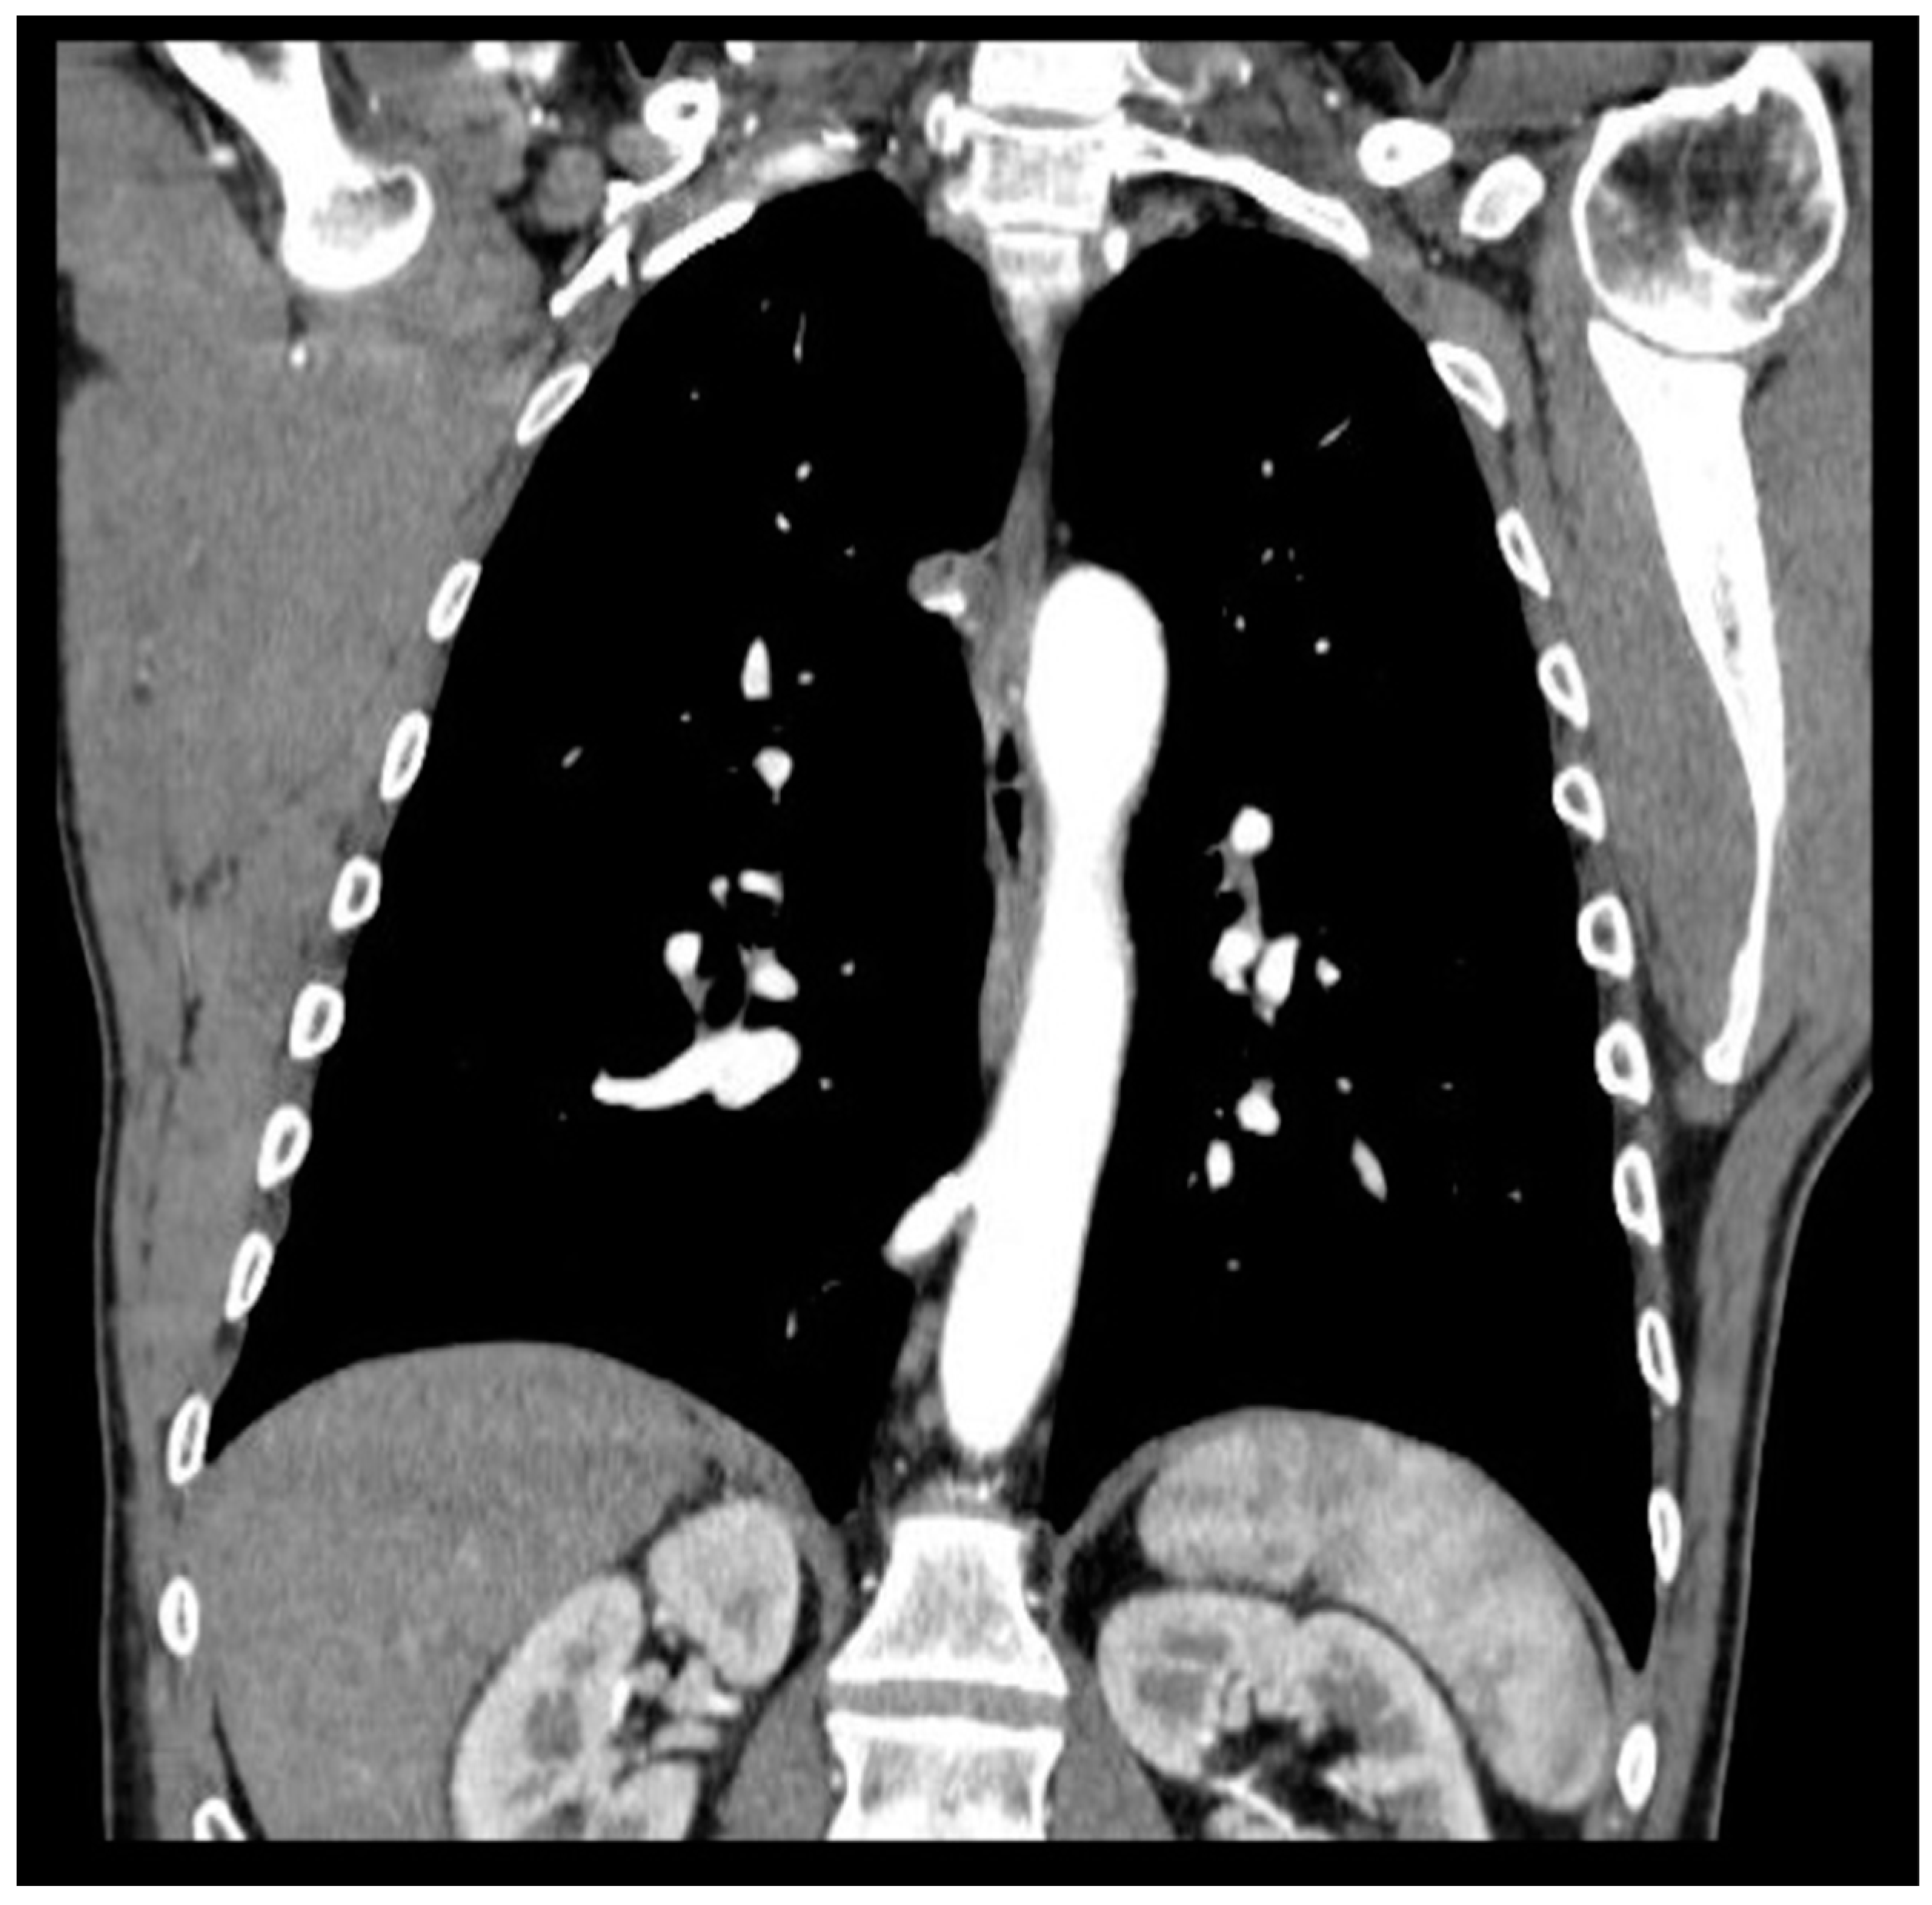

Pulmonary sequestration (PS) represents 0.15–6.45% of CPMs [3]; it is characterized by a mass of non-functioning lung tissue separated from the normal tracheobronchial tree and receiving vascular supply from a systemic artery (Figure 1). It is classified as intra-lobar PS (IL-PS) when it is incorporated in the parenchyma of a lobe and as extra-lobar PS (EL-PS) when it is separated from the adjacent normal parenchyma by its own pleural envelope.

Figure 1. CT evidence of systemic arterial vascularization from descending thoracic aorta.